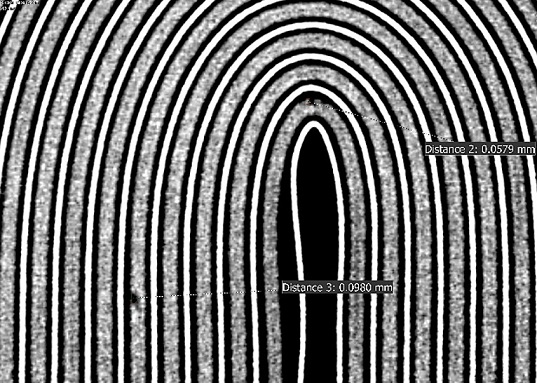

Devil is in the Detail

Datawiz’s experts pioneered the adaptation of microCT (300nm vixel size or smaller) in the consumer electronics and medical devices field more than a decade ago and revolutionized the field. We have established thousands of use cases of microCTs, including detecting structural defects, porosity analysis, fractures and delamination, alloy phases, and many more.

This led to our participation in many innovative and cool projects such as archeology, paleontology, pedology, clean energy, composite materials, additive manufacturing and many more.